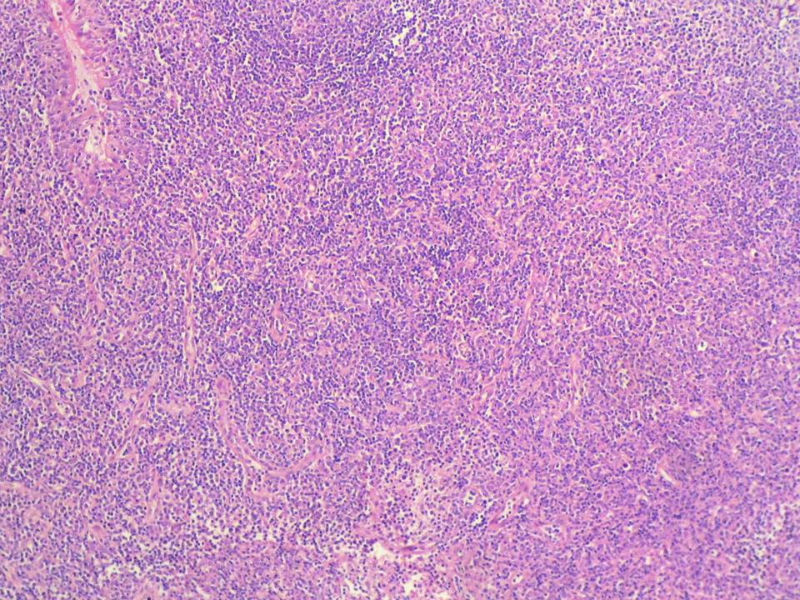

标记树突细胞标志物CD21或CD23或D2-40,可能显示树突网与HE见到的明确的滤泡生发中心一致。

Ki-67标记在淋巴滤泡(生发中心)细胞全阳性,而且显示出生发中心边缘规则,不像是肿瘤,呈反应性增生。

Ki-67标记在滤泡间和淋巴组织弥漫增生区见散在阳性细胞,这些阳性细胞可能是转化性淋巴细胞,有的甚至是内皮细胞或组织细胞。

请看下图,显示的细胞比较杂,胞浆较丰富,胞核没有什么特别的异型性。没有促纤维增生反应和围血管生长表现,没有肿瘤性坏死,没有见到更多的核分裂,特别是病理性核分裂。因此认为,本例是淋巴组织反应性增生,可能是对病毒感染的反应。